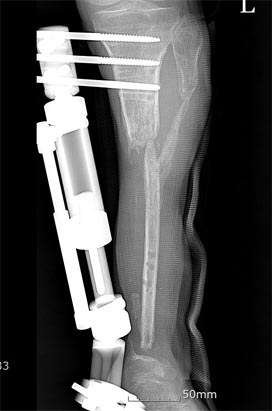

골절부의 외고정 상태를 보여줌.

압궤된 경골 연부조직이 괴사 되면서 골괴사가 되어 골을 제거하고 비골부위를 이식한 후의 X-선 사진.

비골 이식 부위가 약하여 반대편 비골을 혈관과 근육과 같이 이식하여 골유합 된 상태.

측면 X-선 사진임.